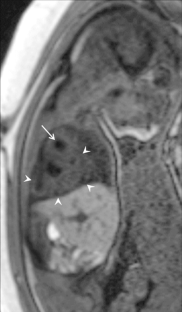

Fig. 1